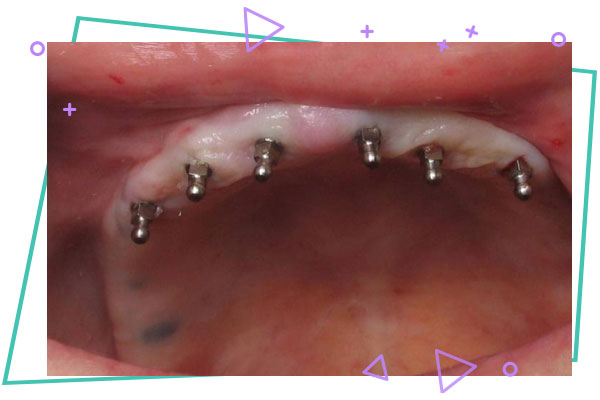

در روش های نوین امروزی در جراحی ، برای اینکه فک ثابت نگه داشته شود ، از پیچ و پلیت هایی استفاده می شود که به بیماران اجازه می دهد بتوانند بلافاصله بعد از عمل ، حرکات عادی فکین را از سر بگیرند ، مثل صحبت کردن ، خمیازه کشیدن یا سرفه کردن. فقط از بیمار خواسته می شود یک رژیم سبک مثل سوپ ، پوره سیب زمینی و غذاهای نرم داشته باشند. تقریبا دوره این رژیم ۶ هفته می باشد تا زمانی که استخوان های فک بدون فشار جوش بخورند و بهبود پیدا کنند .